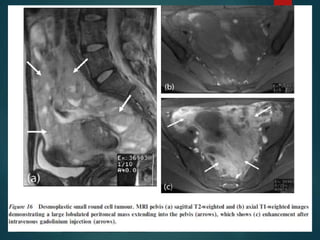

Desmoplastic Small Round Cell

Tumor…

• Rare malignancy of uncertain origin.

• Young men with a mean age of 19 years.

• Consider this diagnosis if we see something

that looks like peritoneal carcinomatosis in a

young man that has no history of a primary

malignancy.

• It is a very aggressive tumor with a poor

prognosis.

Tumor.

Desmoplastic Small RoundCell Tumor… • Rare malignancy of uncertain origin. • Young men with a mean age of 19 years. • Consider this diagnosis if we see something that looks like peritoneal carcinomatosis in a young man that has no history of a primary malignancy. • It is a very aggressive tumor with a poor prognosis.

• #54 It occurs primarily in young men with a mean age of 19 years.

• #55 THEY BEGIN AS A dominant mass and then multiple masses occur within the peritoneum As this stage it is no different upon imaging to other tumors,however age of the patient provides clue for diagnosis. NHL b the close d/d.